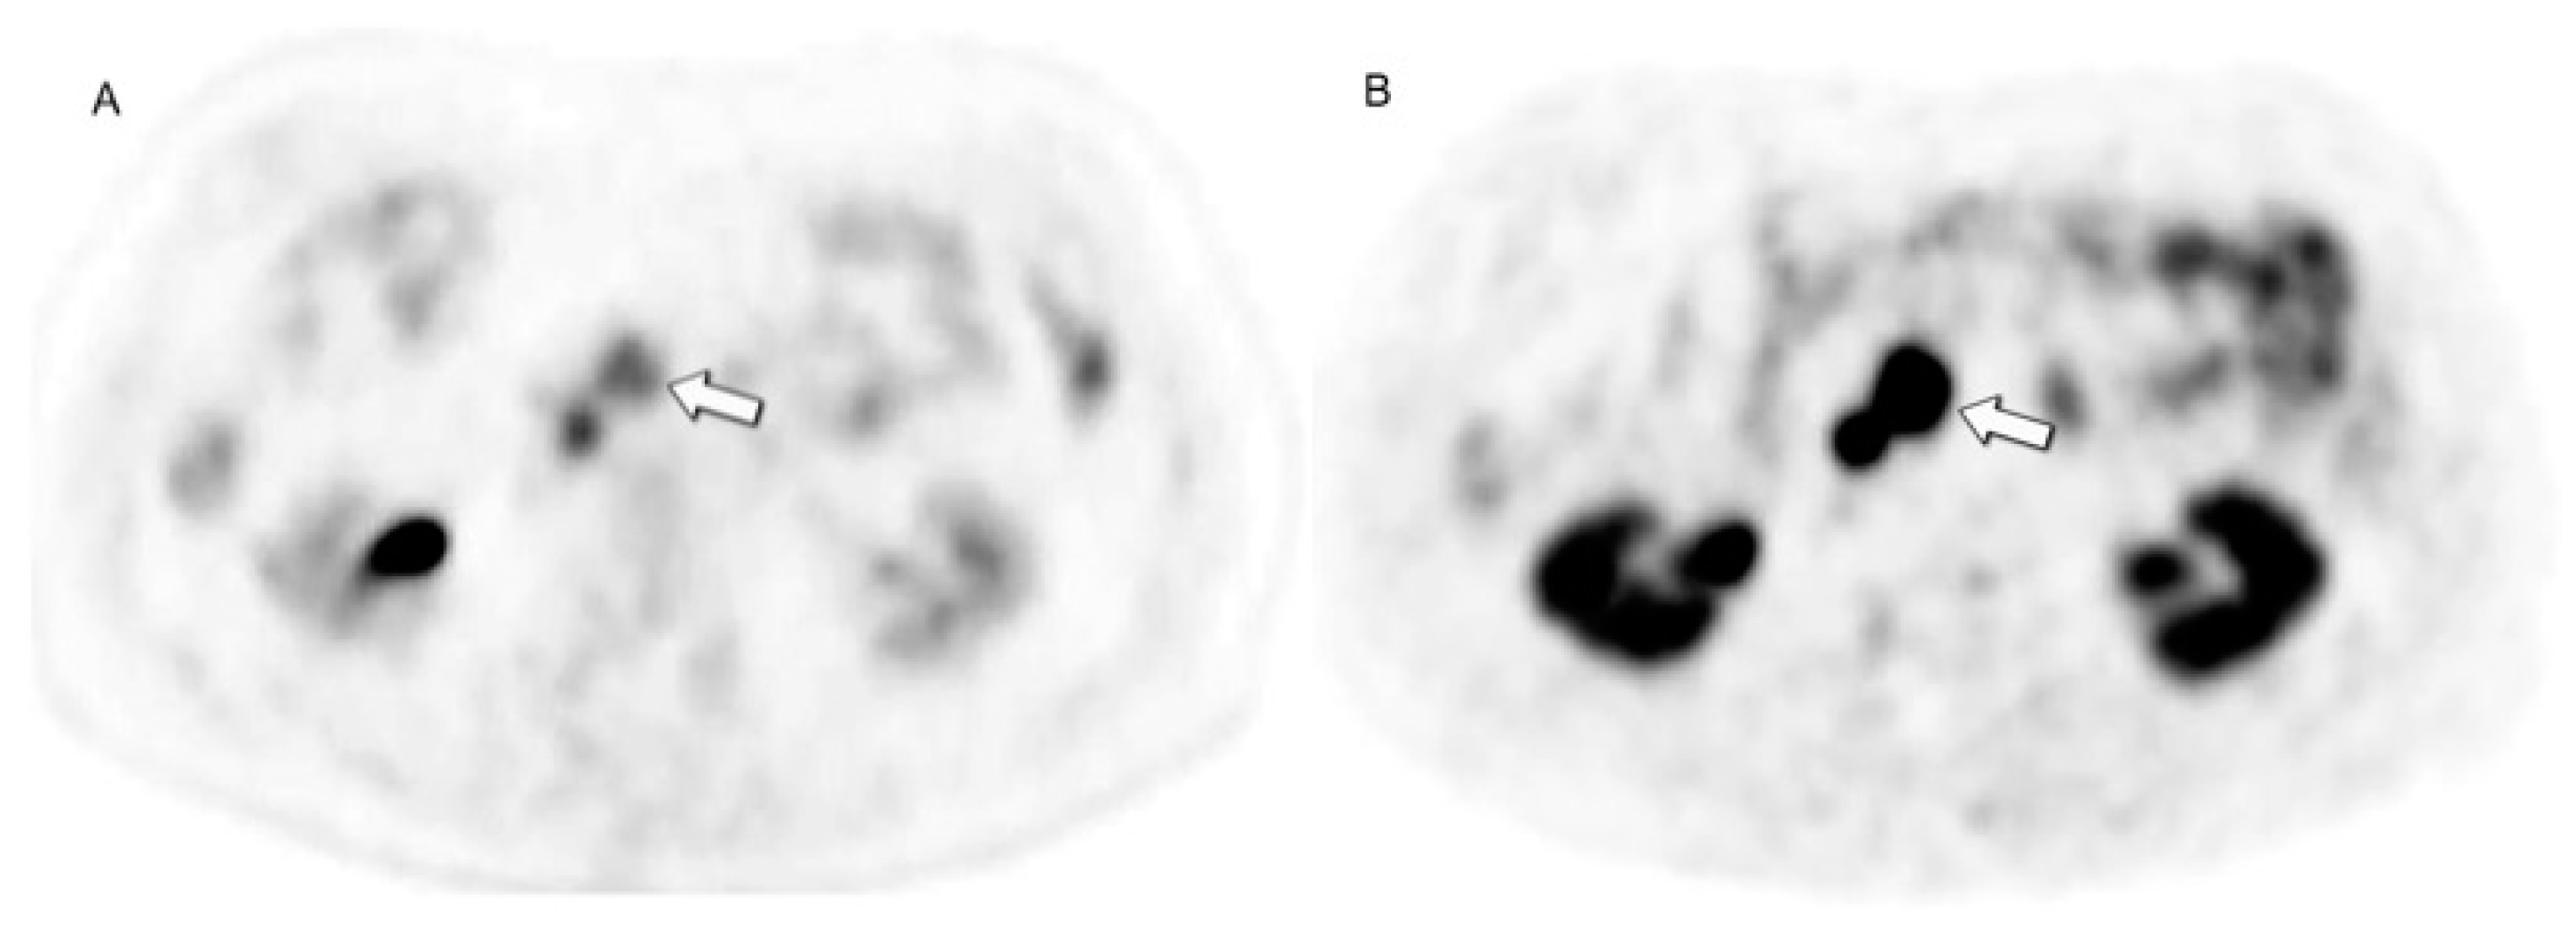

- Cherk, M.H.; Kong, G.; Hicks, R.J.; Hofman, M.S. Changes in Biodistribution on 68Ga-DOTA-Octreotate PET/CT after Long Acting Somatostatin Analogue Therapy in Neuroendocrine Tumour Patients May Result in Pseudoprogression. Cancer Imaging 2018, 18, 3. [Google Scholar] [CrossRef]

- Gålne, A.; Almquist, H.; Almquist, M.; Hindorf, C.; Ohlsson, T.; Nordenström, E.; Sundlöv, A.; Trägårdh, E. A Prospective Observational Study to Evaluate the Effects of Long-Acting Somatostatin Analogs on 68Ga-DOTATATE Uptake in Patients with Neuroendocrine Tumors. J. Nucl. Med. 2019, 60, 1717–1723. [Google Scholar] [CrossRef]